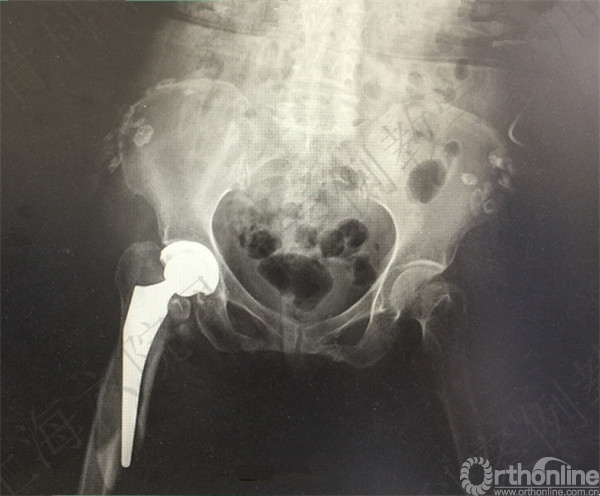

患者跌倒致右股骨颈骨折,择期行右全髋置换术。

术后2周患者自述夜间翻身至右髋疼痛。

急诊X线摄片示:右髋假体脱位,小粗隆骨折。

急诊予全麻下手法复位。

X线摄片示:右髋假体复位,骨折对位对线可,假体无明显松动。